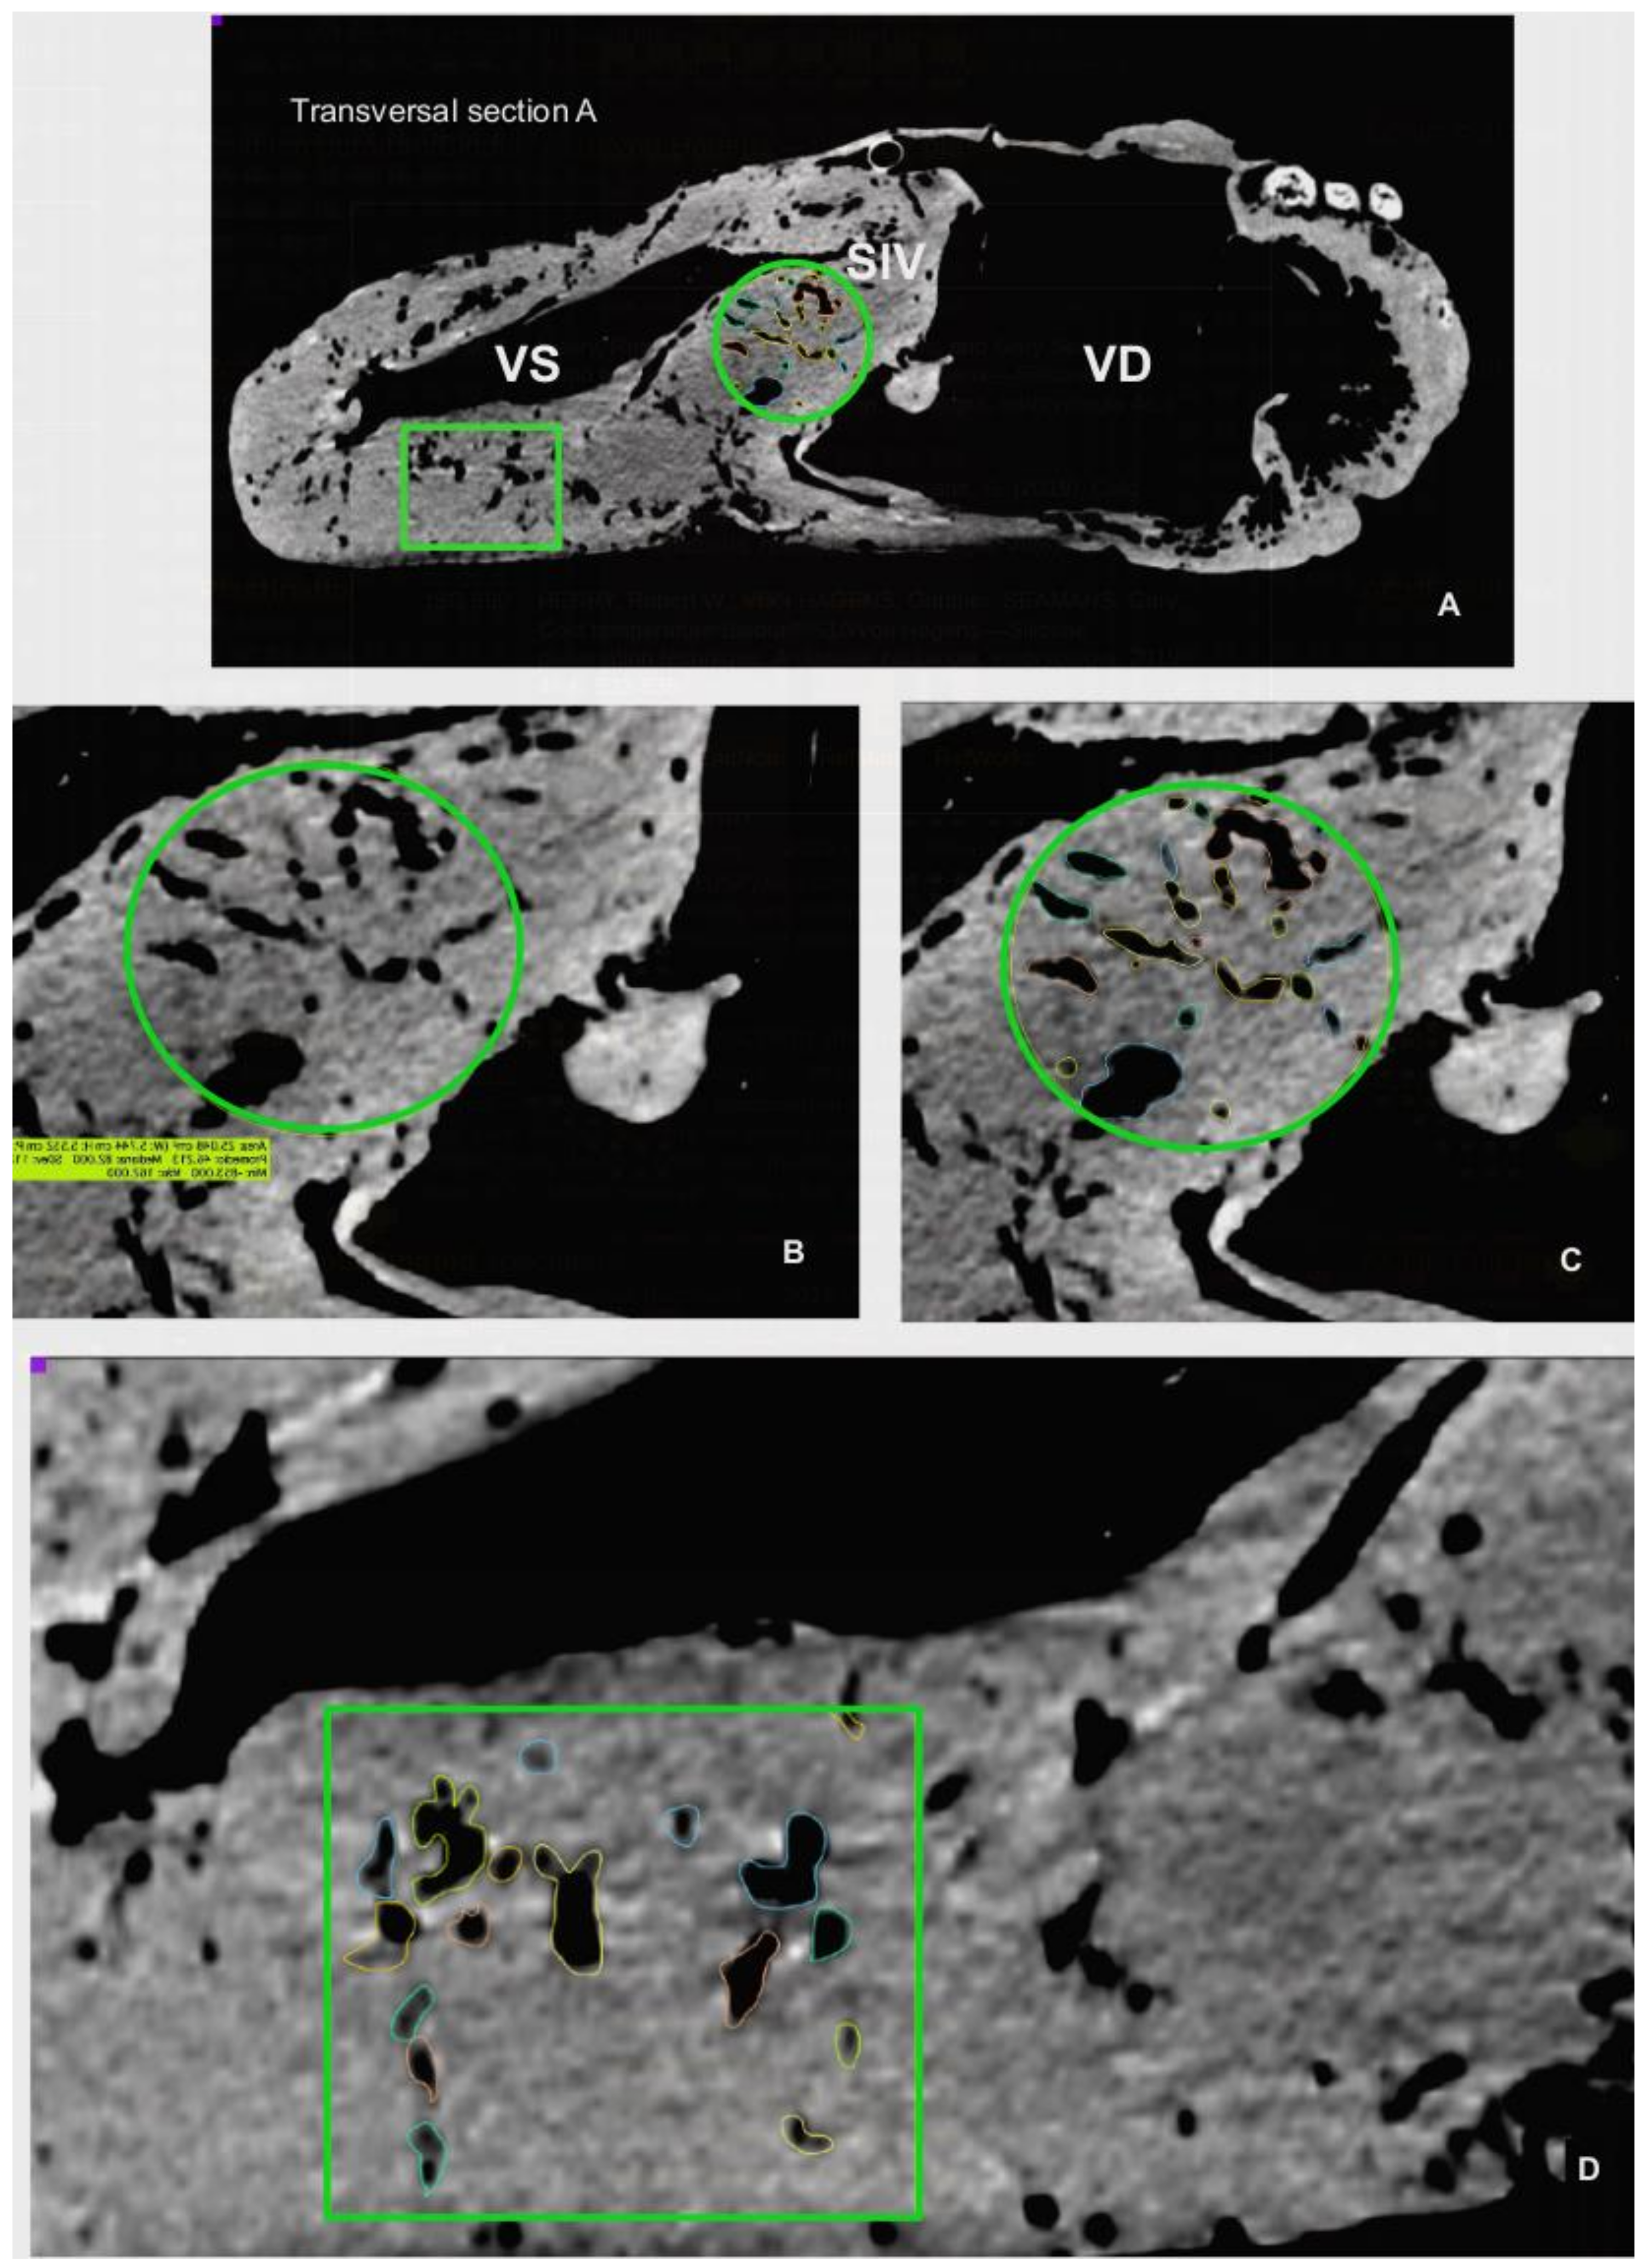

The CT scan images were used to document the morphometry of relevant anatomical landmarks and 3D rendering with the OsiriX Lite® software (v.12.0.1, Pixmeo, Geneva, Switzerland). Besides individual measurements of specific structures, measurements of large anatomical areas, such as the length and thickness of the interventricular septum or the parietal wall and lumen of ventricles, were determined by specific CT images. These reference planes included a CT sagittal plane incorporating the two ventricles and aortic sinus, and CT cross-sectional images at three different levels of the heart: Level I: a transversal section just distal to the atrioventricular valves; Level II: a transversal Section 10 cm distal from level I; and Level III: a transversal section 10 cm distal from level II (Figure 4).

These two grooves correspond to the outer projection of the Septum interventriculare. CT images of the septum identifies two portions, a smaller and thinner Pars membranacea located dorsally (length 4.72 cm and thickness 2.26 cm), and a main Pars muscularis, which internally separates both ventricles. The thickness of the Pars muscularis varies throughout its length; it is 9.56 cm (area 77.78 cm2) at level I, 4.72 cm (area 64.16 cm2) at level II, and 6.20 cm (area 49.07 cm2) at level III. In the sagittal plane, its length is 31.59 cm with an area of 184.45 cm2 (Figure 4).

The left and right ventricles are circumscribed by the parietal wall. In the right ventricle, the length of the parietal wall in the reference sagittal plane is 45.04 cm, the area is 126.79 cm2, and the ventricular luminal area is 325.59 cm2. In the reference transversal cross-sections, the corresponding length and area of the parietal wall and ventricle lumen cavity are as follows: Level I: 2.77 cm, 102.28 cm2, 197.18 cm2; Level II: 3.27 cm, 102.48 cm2, 145.99 cm2; Level III: 4.90 cm, 68.85 cm2, 36.17 cm2. Conversely, in the left ventricle, the reference sagittal plane wall length is 40.57 cm, the mural area is 187.87 cm2, and the cavity or luminal area is 133.05 cm2. In cross-sections, the length and area of the wall and ventricle lumen cavity are as follows: Level I: 5.06 cm, 184.04 cm2, 33.39 cm2; Level II: 6.29 cm, 132 cm2, 17.42 cm2; Level III: 5.28 cm, 124.42 cm2, 12.54 cm2 (Figure 4).

The CT and endoscopic images revealed intramyocardial vascular caverns within both the interventricular septum and the parietal walls of the ventricles (Figure 6, Figure 8A and Figure 9A). The estimated proportion of myocardial area occupied by these caverns in the interventricular septum is: 13.78% (I), 23.5% (II) and 7.49% (III); in the wall of the right ventricle: 69% (II) and 65.09%, (III); and for the wall of the left ventricle: 11.61%(I), 18.4% (II) and 17.89% (III).

Figure 4. CT (computed tomography) sagittal and transversal sections used for morphometry. (A): Sagittal section through the Sinus aortae, where the two Arteria carotis arise. (B): Transversal section I, just distally to the Valva atrioventricularis (dextra and sinistra). (C): Transversal section II, 10 cm distally to previous section. (D): Transversal section III, 10 cm distally to section II. Aorta ascendens (Aa), Truncus pulmonalis (Tp), Atrium dextrum (AD), Atrium sinistrum (AS), Ventriculus dexter (VD), Ventriculus sinister (VS), Septum interventriculare (SIV): Pars membranacea (SIV Pmb) Pars muscularis (SIV Pm). The selected areas for estimatiion of cavern proportions showed in (B) (Septum interventriculare), and (C,D) (wall of Ventriculus sinister).

Figure 6. (A): Estimation of cavern proportion calculated at the CT transversal section I (Figure 4). (B): Magnification of the 25 cm2 green circled area showed in A. (C): Cavern estimation in selected round area of (B). (D): Cavern estimation in the 25 cm2 green squared area in the Ventriculus sinister (VS) wall showed in Ventriculus dexter (VD), Septum interventriculare (SIV).